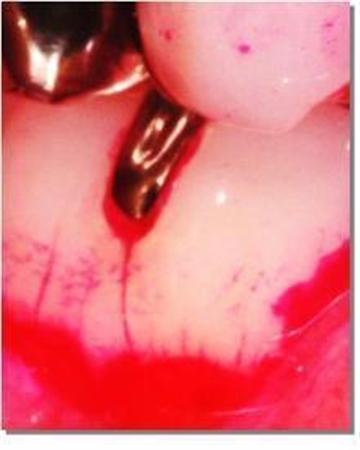

治療した虫歯の充填(じゅうてん)物と歯の境目も汚れが残りやすい。金属充填物をはめた様子